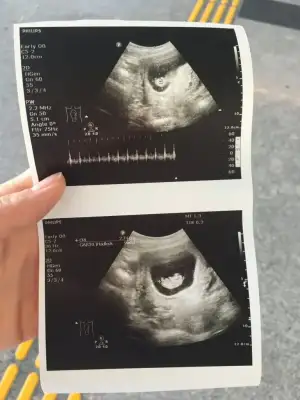

Rica etsem benimkine de bakar mısınız? 10+0 da çekildi 9+3 çıktıEvet ramziye göre erkek